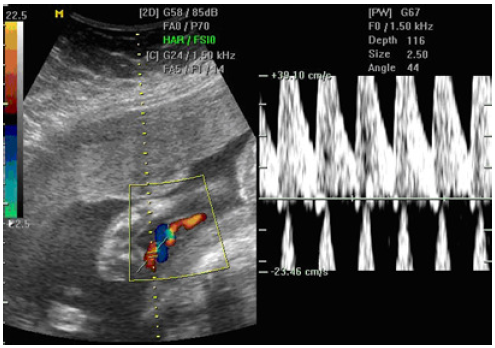

O fenômeno abaixo está relacionado a: